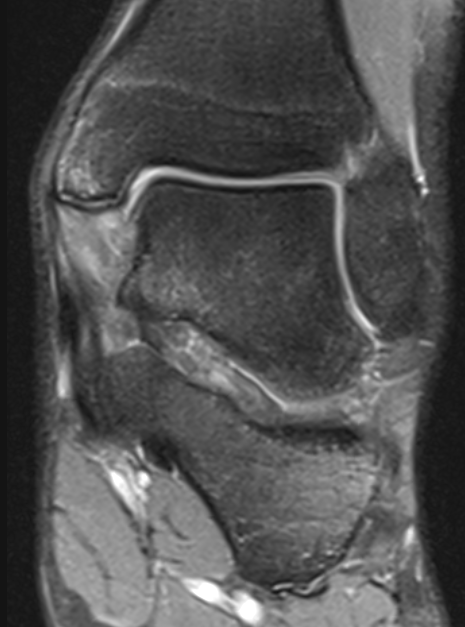

Deep deltoid ligament sprain injury